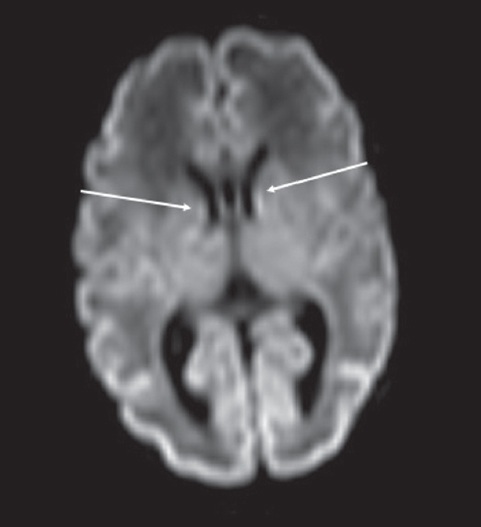

У новорожденных, которым МРТ проводили с 33-й по 34-ю неделю ПКВ, герминальный матрикс визуализировался у двух пациентов на ДВИ в виде слабого повышения МР-сигнала вдоль боковых стенок боковых желудочков мозга (рис. 7). На остальных импульсных последовательностях герминальный матрикс не определялся.

Рис. 7. МРТ головного мозга недоношенного ребенка (ПКВ 34 недели). ДВИ, аксиальная проекция, герминальный матрикс визуализируется вдоль наружных стенок боковых желудочков (отмечен стрелками)

Fig. 7. MRI of preterm newborn (PCA 30 wks.), DWI, axial plane. The germinal matrix is visualized along the external walls of the lateral ventricles (marked by arrows)

На ДВИ субэпендимальный герминальный матрикс выявляется у подавляющего числа недоношенных детей в возрастной группе 27–32 недели ПКВ, у двух недоношенных детей — в возрастной группе 33–34 недели ПКВ. Герминальный матрикс на ДВИ-последовательности визуализируется в виде локального гиперинтенсивного сигнала в области передних отделов боковых желудочков и гиперинтенсивного линейного сигнала в области наружного края боковых желудочков (частично повторяющего контур наружной стенки желудочка). Чувствительность ДВИ в визуализации герминального матрикса превышает другие импульсные последовательности МР и позволяет получить более полную визуализационную картину регрессии субэпендимального герминального матрикса в вентрикулярных зонах головного мозга недоношенных детей.